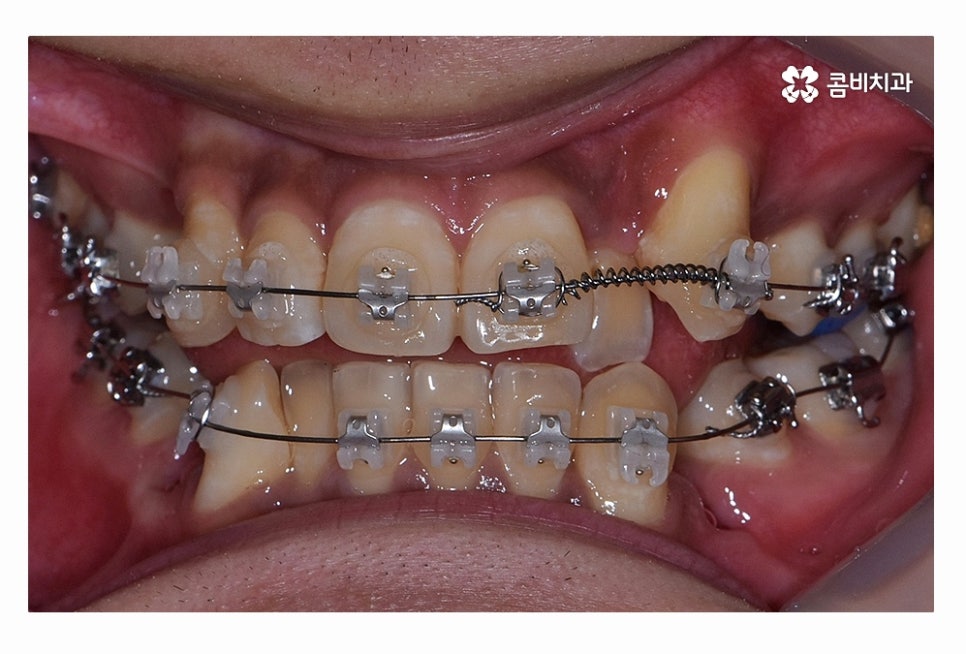

오늘 보시는 환자분의 사례처럼 덧니가 치아끼리 겹쳐 있는 경우에

치아의 이동 공간 확보를 위해서 덧니 발치 필요한 사례였으며

교합과 치아교정 후 얼굴 변화를 고려할 때도 치아교정 과정에서

발치가 필요한 사례였다고 볼 수 있어요.

치아교정 과정에서 덧니 발치 필요한 경우에는 덧니 자체를

발치한다고 생각하시는 분들도 계신데

꼭 그렇지는 않으며 앞서 설명드린 것처럼

치아의 이동 공간 확보와 교합을 고려하여 발치가 이뤄지고 있어요

일반적으로는 송곳니 옆의 작은 어금니를 발치하는

경우가 대부분이며 손상이 심한 치아가 있는 경우에는

손상도가 심한 치아를 발치하는 경우도 있어요